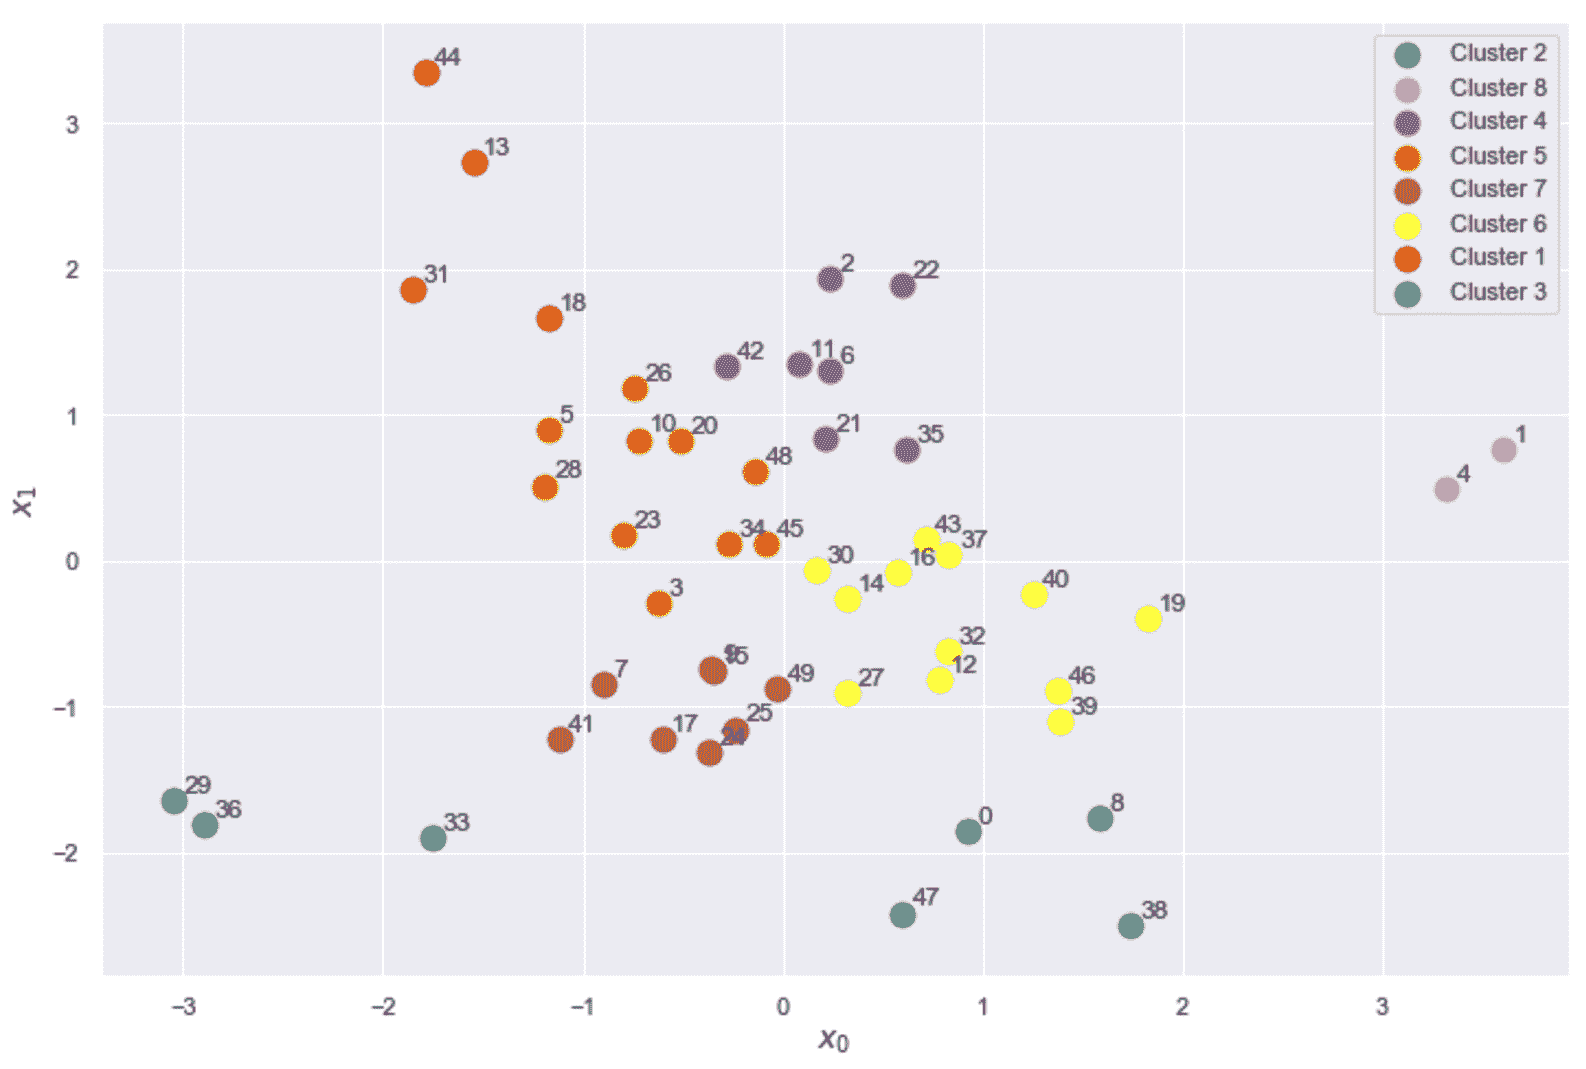

生成的绘图显示在以下屏幕截图中:

乳腺癌威斯康星州数据集的 K 均值聚类(K = 8)结果

现在,让我们考虑位于图底部的子群集(-25 < x < 30和-60 < y < -40) , 如下:

乳腺癌威斯康星州数据集的轮廓图

第一张图显示了K = 2的自然聚类。 第一个轮廓非常清晰,表明平均群集间距离具有较大的差异。 而且,一个集群比另一个集群具有更多的分配(即使它不那么尖锐)。 从数据集描述中,我们知道这两个类别是不平衡的(357 良性与 212 恶性),因此,不对称是部分合理的。 但是,一般而言,当数据集平衡时,良好的轮廓图的特征是具有均匀轮廓的均质群集,其圆形轮廓应接近 1.0。 实际上,当形状类似于长雪茄时,这意味着群集内距离非常接近其平均值(高内聚),并且相邻群集之间存在明显的分隔。 对于K = 2,我们拥有合理的分数,因为第一个群集达到 0.6,而第二个群集具有约 0.8 的峰值。 但是,尽管后者的大多数样本的特征是s(•) > 0.75,但在前一种样本中,约有一半的样本低于 0.5。 分析表明,较大的聚类更均匀,并且 K 均值更易于分配样本(即,就度量而言,x[i] ∈ K[2]的方差较小,在高维空间中,代表K[2]的球比代表K[1]的球更均匀。)。

其他图显示了类似的情况,因为已检测到非常紧密的聚类以及一些尖锐的聚类。 这意味着宽度差异非常一致。 但是,随着K的增加,由于分配的样本数趋于变得相似,因此我们获得了更加均一的群集。 具有s(·) > 0.75的非常圆形(几乎矩形)的群集的存在证实了数据集至少包含一组非常有凝聚力的样本,相对于分配给其他群集的任何其他点的距离都非常接近。 我们知道,恶性类(即使其基数更大)更为紧凑,而良性类则分布在更宽的子空间中。 因此,我们可以假设,对于所有K来说,最圆的群集是由恶性样本组成的,而其他所有群集都可以根据其清晰度进行区分。 例如,对于K = 8,第三群集很可能对应于第一图中第二群集的中心部分,而较小的群集包含属于良性子集的孤立区域的样本。

如果我们不了解基本事实,则应同时考虑K = 2和K = 8(甚至更大)。 实际上,在第一种情况下,我们可能会丢失许多细粒度的信息,但是我们正在确定一个强大的细分领域(假设由于问题的性质,一个集群的凝聚力不是很高)。 另一方面,在K > 8的情况下,群集明显更小,具有适度的内聚性,它们代表具有某些共同特征的亚组。 正如我们在上一节中讨论的那样,最终的选择取决于许多因素,这些工具只能提供一般的指示。 此外,当聚类是非凸的或它们的方差未在所有特征之间均匀分布时,K 均值将始终产生次优表现,因为所得聚类将包含较大的空白空间。 如果没有特定的方向,则群集的最佳数量与包含均匀(宽度大致相同)的圆形图的图相关联。 如果形状对于任何K值仍然保持清晰,则意味着几何形状与对称度量不完全兼容(例如,群集非常拉伸),应考虑其他方法。